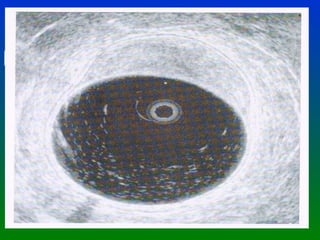

CANCER DE RECTO DIAGNOSTICO ANNALS OF ONCOLOGY SUPLEMENTO OCT. 2002 El Ultrasonido endorrectal es la mejor herramienta Para evaluar la invasión tumoral en la pared rectal. Con un elevado % de sensibilidad y especificidad. UT 1 Invasión hasta la muscularis mucosa UT 2 Invasión hasta la muscularis propia PT 1 Confinado a la grasa submucosa * En estas condiciones la mejor elección es una  Excisión local

CANCER DE RECTODIAGNOSTICO ANNALS OF ONCOLOGY SUPLEMENTO OCT. 2002 El Ultrasonido endorrectal es la mejor herramienta Para evaluar la invasión tumoral en la pared rectal. Con un elevado % de sensibilidad y especificidad. UT 1 Invasión hasta la muscularis mucosa UT 2 Invasión hasta la muscularis propia PT 1 Confinado a la grasa submucosa * En estas condiciones la mejor elección es una Excisión local